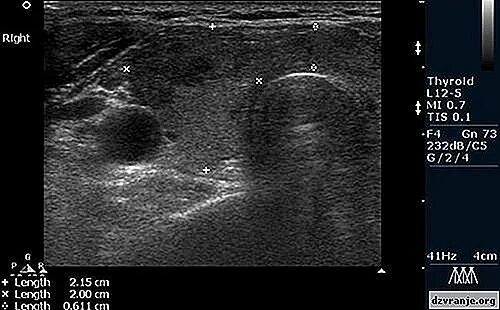

Выраженные диффузные изменения щитовидной железы